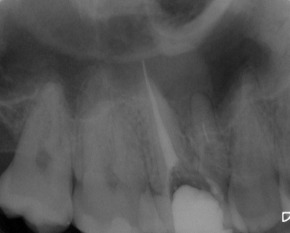

Nach erfolgter Information über die vermutete Prognose unternehmen wir den Versuch, das frakturierte Instrument darzustellen. Nach Entfernung der Aufbaufüllung werden die Kanaleingänge dargestellt (Abb. 2). Es zeigt sich, dass neben dem distovestibulären Kanal auch ein vierter Kanal (mb2) vorhanden ist. Die Darstellung der Wurzelkanaleingänge erfolgt in unserem Haus mit dem Aufsatz 1R des Tigon+. Dank der Abwinkelung des Instruments profitiert man von einer sehr guten Sicht auf die Behandlungsstelle. Zudem erlaubt es ein schnelles und gezieltes Abtragen von Dentin, ohne dabei den Zahn unnötig zu schwächen.

Abb. 2: Darstellung aller Wurzelkanaleingänge. Die palatinale Wurzelfüllung wird belassen, da sie für gut befunden wird.